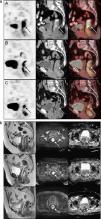

MethodsOut of 20 LARC patients, who were planned to receive neoadjuvant RCT, 19 were included in this prospective study. Patients had 18F-FDG PET/CT and DW-MRI at initial staging, interim (2 weeks after onset of RCT) and after completion of RCT (post-therapy). Standardized uptake value (SUV) parameters (SUVmax, SUVmean, SUVpeak, SULpeak), metabolic tumor volume (MTV) and tumor lesion glycolysis (TLG) detected on PET images and apparent diffusion coefficient (ADC) values (for b=400 and b=1000s/mm2) obtained from DW-MRI were recorded. Postoperative tumor regression grade (TRG) was used as gold-standard, except for 2 patients who were under complete remission with non-operative management 19 months post-therapy and scored as responders.

ResultsOn interim PET/CT, no significant difference was found among PET parameters between responders and non-responders, whereas post-therapy SUVmax, SUVpeak, MTV, SULpeak, TLG (p=0.02, p=0.014, p=0.025, p=0.007, p=0.02, respectively) and initial MTV (p=0.034) were significantly lower in responders. ADC response index (RI) was higher in responders (interim p=0.026; post-therapy: p=0.018) and ROC analysis revealed that a threshold of ADC RI>41.6% for interim MRI and >44.6% for post-therapy MRI had sensitivity and specificity of 75.0% and 90.9%, respectively.

ConclusionsWhile interim 18F-FDG PET/CT failed to predict therapy response during RCT, post-therapy PET could accurately differentiate responders. DW-MRI was found to be more promising in interim detection of RCT response.